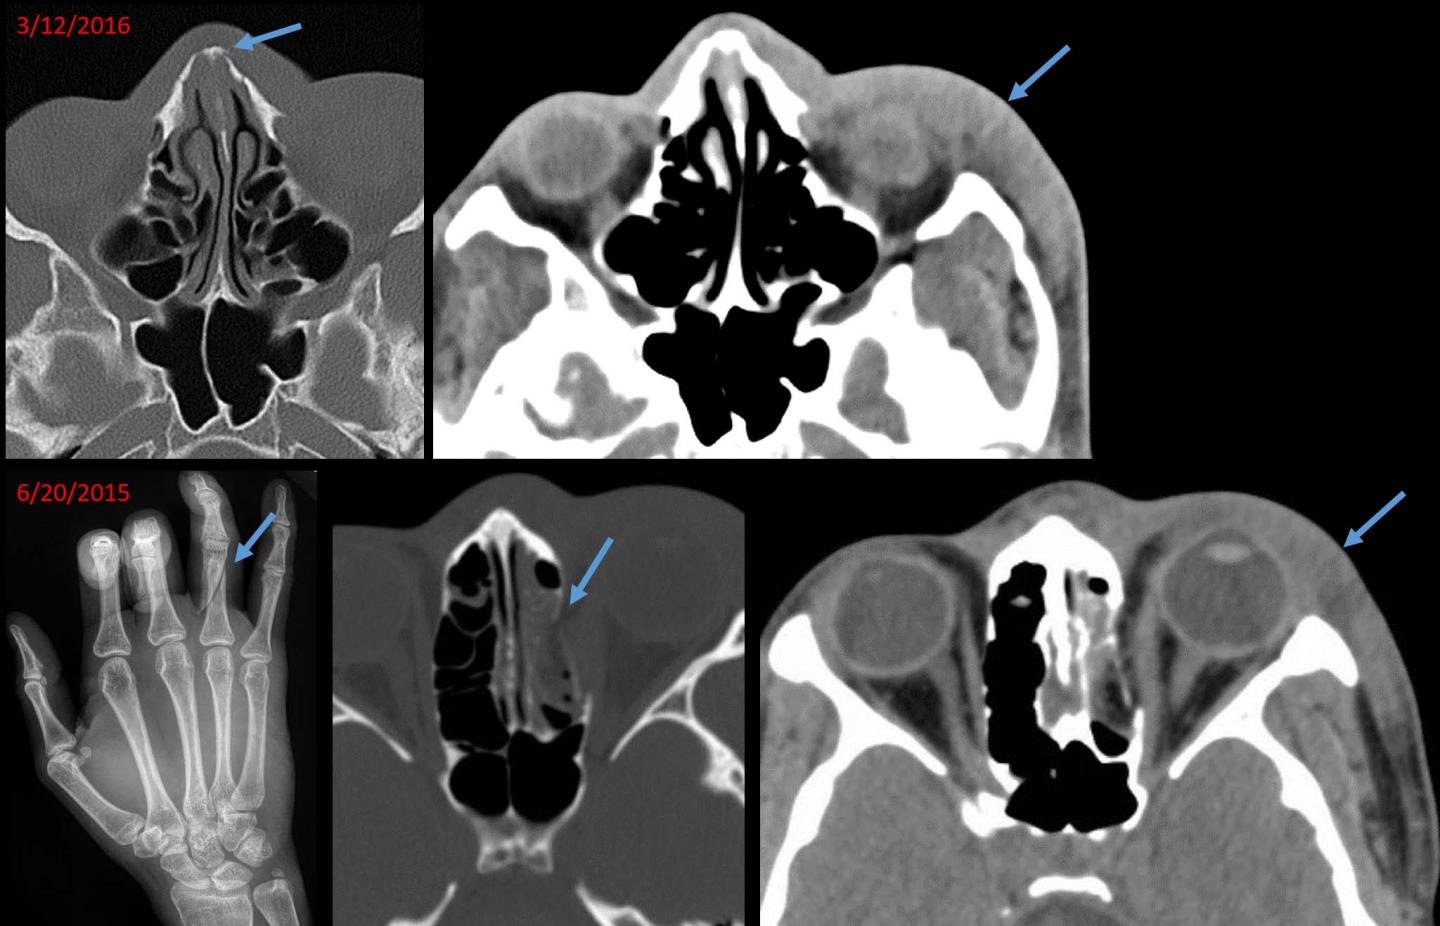

Medical images sometimes offer early clues that abuse is taking place. In fact, the case that inspired the study's principal investigator, Bharti Khurana, M.D., emergency radiology fellowship program director at Brigham and Women's Hospital., involved a young woman who arrived at the Emergency Department with an acute nasal bone fracture superimposed on an old, healed fracture. While going through prior medical images of the patient on the hospital's picture archiving and communication system, or PACS, Dr. Khurana identified a recent wrist fracture. This pattern of recurrent injury made her voice her suspicion of intimate partner violence, a finding the referring physician initially had not suspected.

Along with providing information on presenting injuries, radiologists have access to a wealth of information through PACS that can show prior fractures linked to abuse. Old, healed fractures look distinct from acute fractures, Dr. Khurana said, and may be evident in the form of bone remodeling, deformity or focal bone thickening.

"In the emergency room setting, the priority is to identify acute pathologies," she said. "As a result, old fractures or fracture-related deformities may not be given sufficient importance. But the presence of old and acute fractures may be pivotal in making the diagnosis of intimate partner violence."